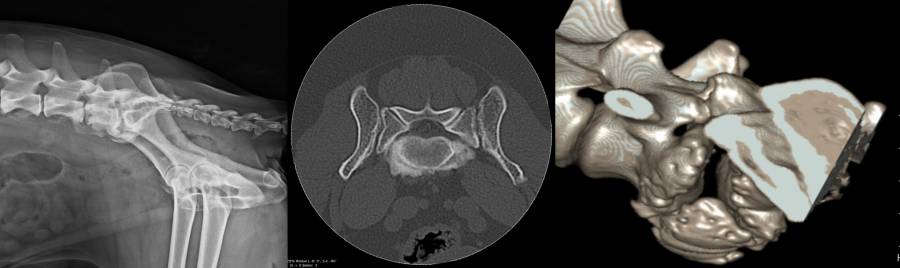

- Röntgen: Hüftbeugung und Hüftstreckung

- CT / MRT